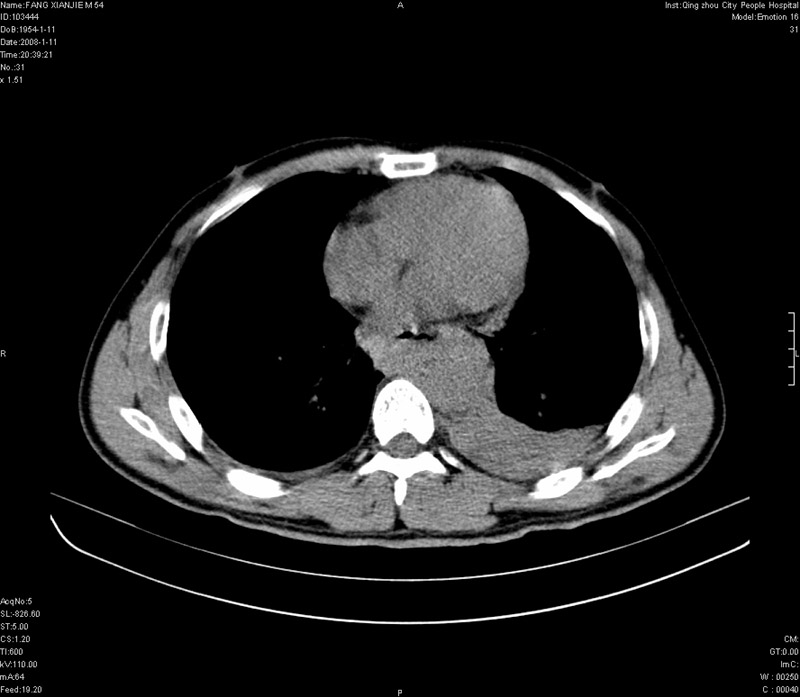

男性,40岁。胸部被车压伤伴胸痛1小时来院就诊。检查:一般情况尚可,血压110/80,胸部及上腹部压痛。结果在三天后公布。骨窗在横断位、冠矢状显示肋骨、胸椎、和胸骨未见骨折征象。

ct11308:胸部外伤1小时(证实病例) (2008-1-13 16:2)结果如下:病人入院后两小时后症状加重,8小时后在征得病人家属同意做了ct增强扫描。如下图。最终临床诊断:外伤性胸主动脉破裂并纵隔内血肿。由于有运动性伪影,胸骨在矢状面重建的图像似有骨折征,这是一种假象,我们称之为“假骨折”,这在多层ct重建中经常性遇到,必要时要结合横断图像鉴别之。现在,病人的一般情况较差,是否要手术家属尚有争议,如果手术修补,难度较大,需要专门预定制作固定支架。

当然,对于该病例,其它非重要的诊断还有:右侧少量气胸;左侧胸腔积液;左侧轻度肺挫裂伤。对于纵隔内血肿,我们曾经遇到过多例,也有怀疑主动脉的破裂,但是,均未得到具体出血部位的明确诊断。